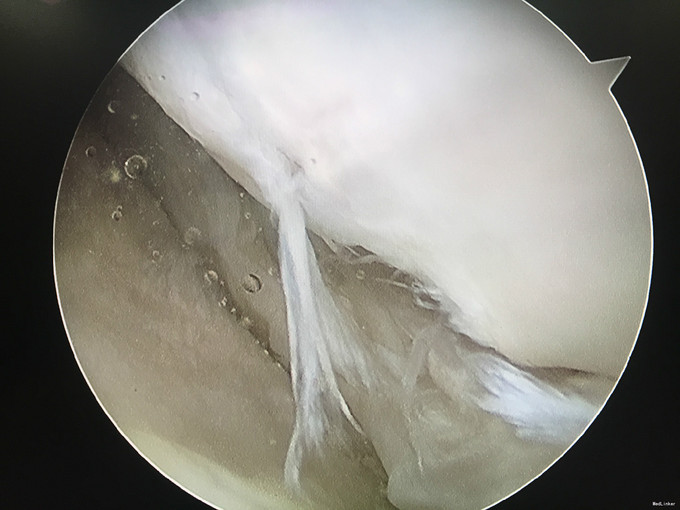

入院诊断:左膝半月板损伤、左膝前交叉韧带损伤 治疗:入院后行左膝关节镜下外侧半月板成形+髁间窝成形+前交叉韧带自体肌腱重建手术。

随访:患者因为病程较长(十余年),术后3月膝关节才恢复正常活动度,行走正常。建议其术后1年再恢复正常运动。 讨论:该病例膝关节损伤时间较长,手术时关节已表现为提早退变(患者年龄并不大)。在前交叉韧带重建前,需要对其狭窄的髁间窝进行成形。术后恢复时间也较一般情况下延长。因此,建议关节出现病损应及时诊治。